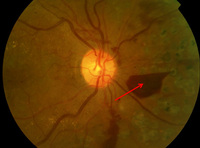

Proliferative diabetic retinopathy: retrohyaloid haemorrhage (red arrow), venous beading (blue arrow), cluster haemorrhage (white circle), pan-retinal laser burns (black arrow)

Courtesy of Moorfields Photographic Archive; used with permission